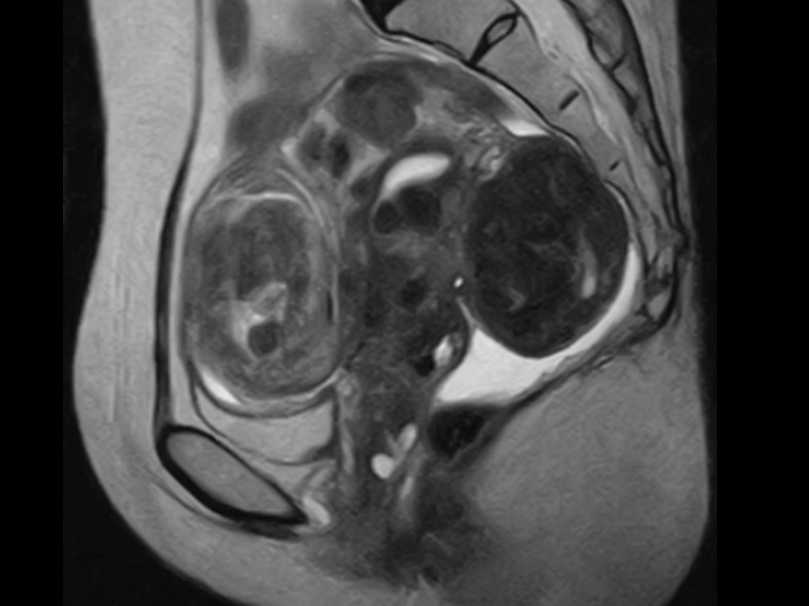

レディースMRI画像

3|レディースMRIドック

生理痛や貧血などの原因となる子宮筋腫や子宮内膜症、がんの発生しやすい子宮体部や、のう腫やがんが発生しやすい卵巣を無痛で、着衣のまま、エックス線照射なしでチェックします。

所要時間:30分  費用:22000円(消費税込み)